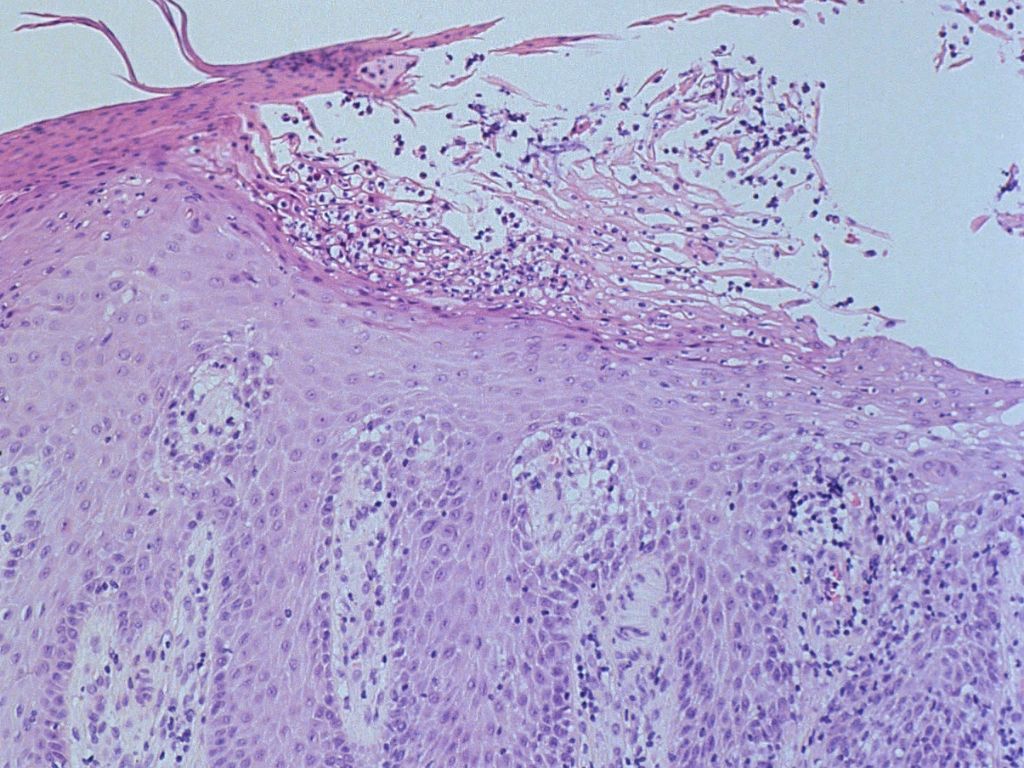

Hallopeau

(PA) |